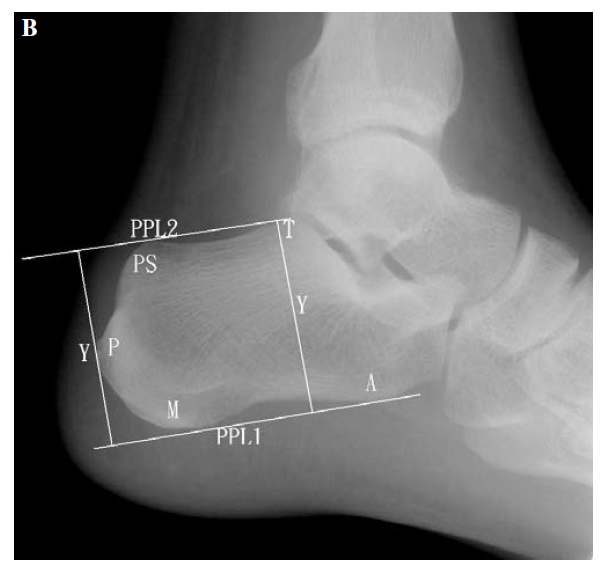

X:Fowler and Philips angle,44°-69°

CLA角:Chauveaux-Liet  Angle,CLA=α-β,>12°怀疑,X/Y值:<2.5高度怀疑

FPA和PPL不可靠,Haglund综合征与跟腱钙化和跟骨后方骨刺关系密切。

X/Y由小于2.5到大于2.5